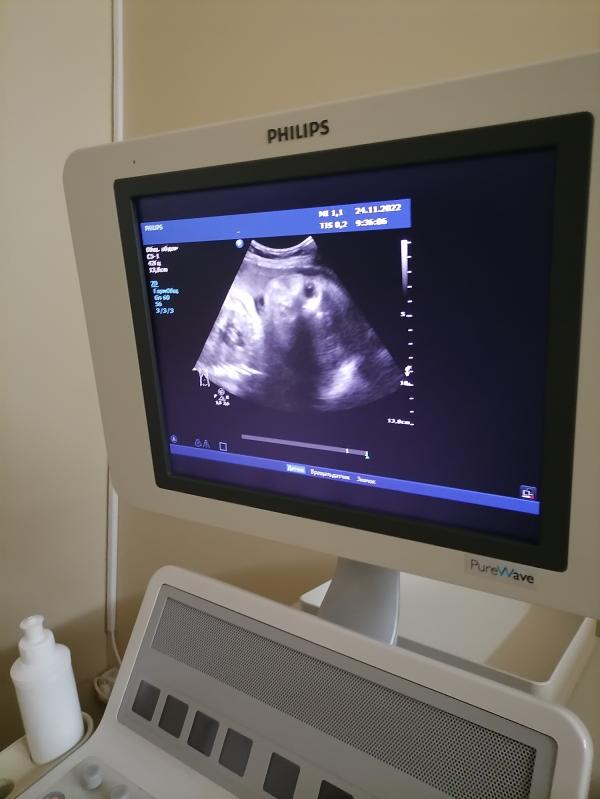

Моя инопланетянка, уже большая, и плохо видно, ещё и отвернулась🙈🥰сходила на 3 скрининг. Всё хорошо у малышки 🙏 Весит примерно 1800))Осталось ещё немножко, и будем нянчится. Срок правда сдвинулся, сегодня 32.2 дня, а по узи 31.3. Показали личико, ручки, ножки, сказали у вас прекрасная малышка🥰

Так здорово!!! Очень рада за вас))) вроде недавно только сообщили о беременности, а уже 32 недели🙈)))

Время летит, вот только про беременность первый пост был, уже третий скрининг😀